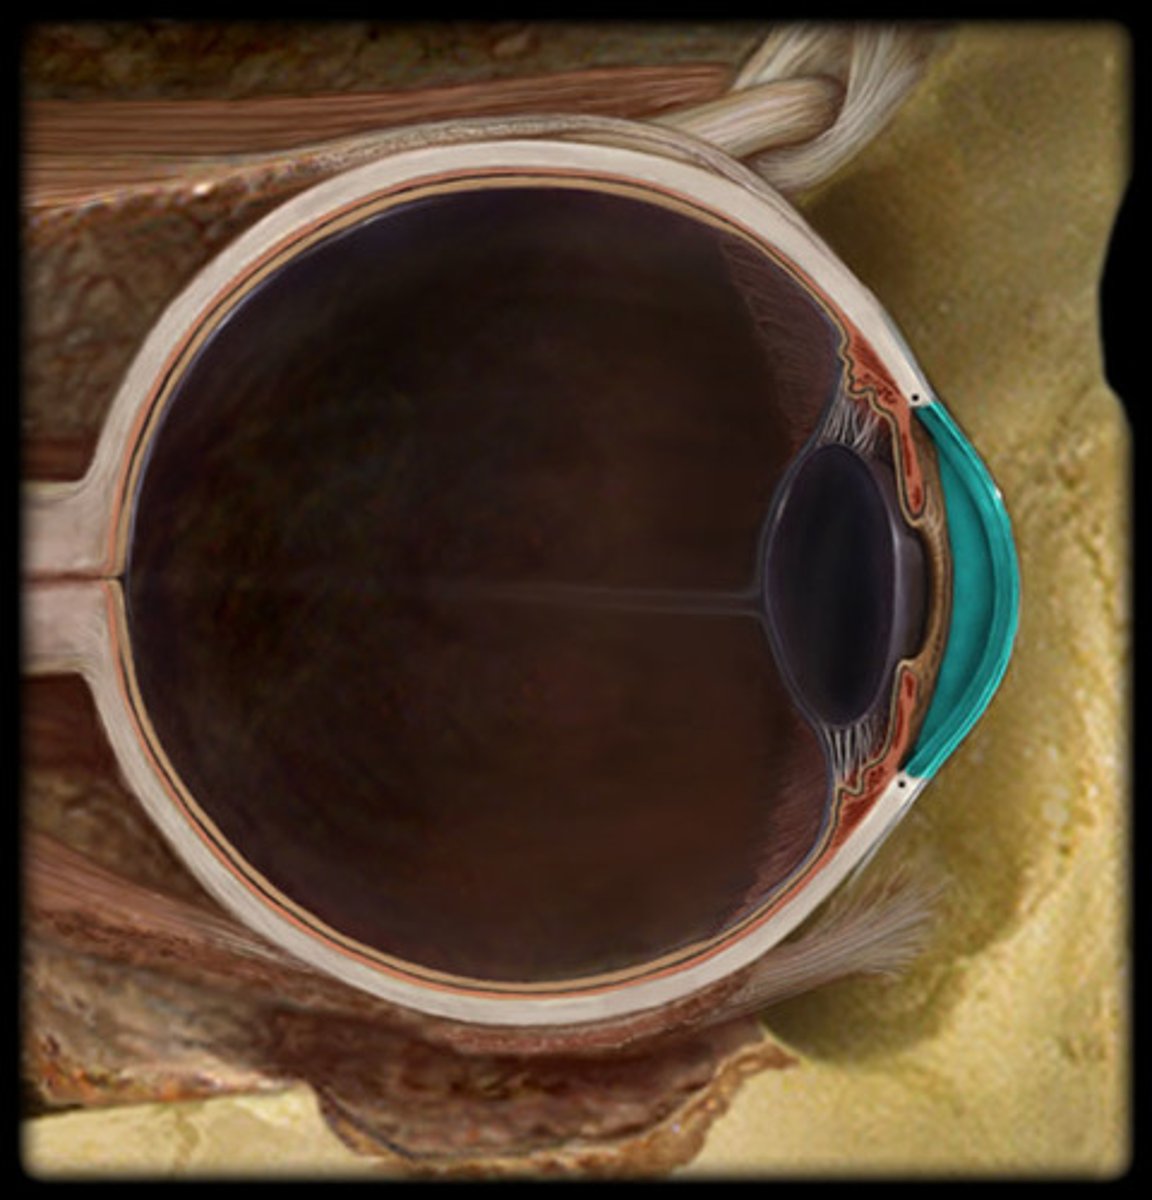

anterior chamber

posterior chamber

ciliary body

cornea

iris

lens

pupil